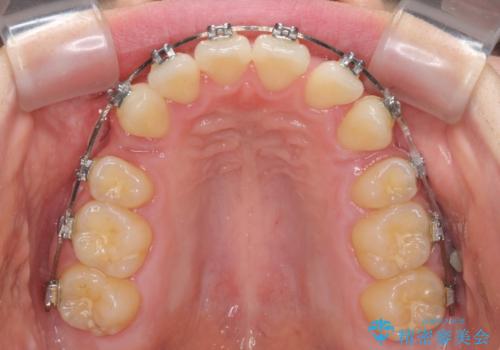

上顎のみの抜歯矯正 前歯のデコボコを改善する

- 上顎前歯のデコボコを気にして来院された患者様です。

口元の突出感はなく、上顎のみに顕著な叢生が認められました。

上顎の左右第一小臼歯2本を抜歯し、ワイヤー装置にて歯列を整えることとしました。

奥歯の咬み合わせがなかなか定まらず、スペースが閉じるまでに時間がかかりましたが、最終的には正中を合わせることもできました。